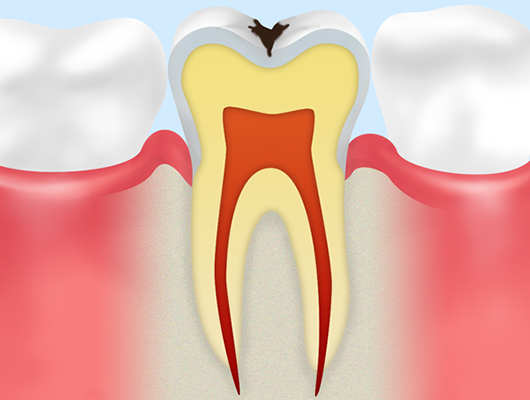

象牙質むし歯(C2)エナメル質の奥にある象牙質にまでむし歯が進行した状態です。肉眼でみても歯に穴があいている様子や黒っぽく変色している様子が確認できます。この段階になると「冷たいものがしみる」など、むし歯特有の症状がはっきりあらわれるようになります。 |